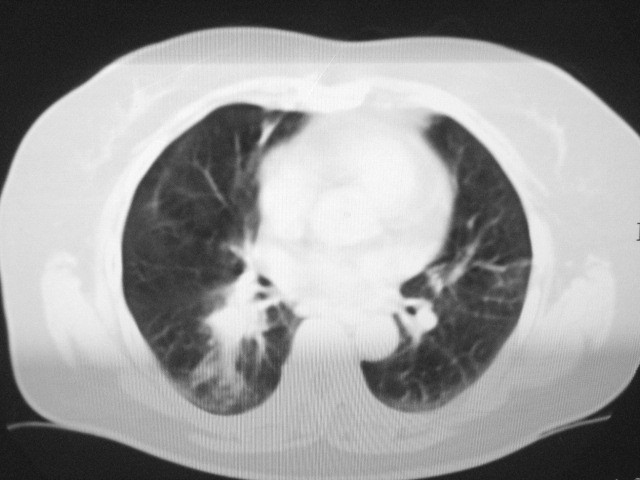

以下是引用清清楚楚在2007-8-28 7:13:00的发言:[br]右肺下叶可见斑片状高密度影,边缘模糊;右肺中叶内侧段及左肺舌段亦可见小斑片状模糊影。[br]考虑双肺感染,建议抗炎治疗后复查。

以下是引用天南地北在2007-8-27 23:49:00的发言:[br]右肺下叶可见斑片状高密度影,边缘模糊;右肺中叶内侧段及左肺舌段亦可见小斑片状模糊影。[br]考虑双肺感染,建议积极抗炎治疗后复查。

以下是引用天南地北在2007-8-27 23:49:00的发言:[br]右肺下叶可见斑片状高密度影,边缘模糊;右肺中叶内侧段及左肺舌段亦可见小斑片状模糊影。[br]考虑双肺感染,建议抗炎治疗后复查。

以下是引用难听在2007-8-28 13:17:00的发言:[br]右肺下叶背段支气管狭窄,是否可以考虑新生物伴阻塞性肺炎.请大家帮帮忙,这个病人是卫生局长的丈母娘.惹不起啊.